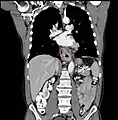

Although an occlusive tumor may be suspected on a barium swallow or barium meal, the diagnosis is best made with an examination using an endoscope. This involves the passing of a flexible tube with a light and camera down the esophagus and examining the wall, and is called an esophagogastroduodenoscopy. Biopsies taken of suspicious lesions are then examined histologically for signs of malignancy.

Additional testing is needed to assess how much the cancer has spread (see § Staging, below). Computed tomography (CT) of the chest, abdomen and pelvis can evaluate whether the cancer has spread to adjacent tissues or distant organs (especially liver and lymph nodes). The sensitivity of a CT scan is limited by its ability to detect masses (e.g. enlarged lymph nodes or involved organs) generally larger than 1 cm.[44][45] Positron emission tomography is also used to estimate the extent of the disease and is regarded as more precise than CT alone.[46] PET/MR as a novel modality has shown promising results in preoperative staging with fair feasibility and good correlation in comparison to PET/CT. It can enhance tissue differentiation with lowering the radiation dose to the patient.[47] Esophageal endoscopic ultrasound can provide staging information regarding the level of tumor invasion, and possible spread to regional lymph nodes.

Endoscopy and radial endoscopic ultrasound images of a submucosal tumor in the central portion of the esophagus- Contrast CT scan showing an esophageal tumor (axial view)

- Contrast CT scan showing an esophageal tumor (coronal view)